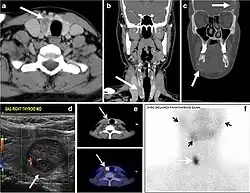

Fig. 17. Ectopic thyroid on the left parotid gland with a palpable left parotid mass in a 69-year-old male patient. a, b Axial and coronal enhanced neck CT scan demonstrates well-defined homogeneous enhancing mass (white arrows) within the left parotid gland with preserved surrounding fat planes. It also shows a normal thyroid in normal position in the lower neck. c Image taken 20 minutes after 5 mCi injected Tc99m-Pertechnetate shows normal thyroid uptake of tracer and physiological uptake in the salivary glands (short black arrow). There is a distinct focus of abnormal tracer accumulation in the left parotid/submandibular region. Patient was given lemon juice with evident normal washout from the salivary glands and relative retention by this abnormal focus (long black arrow).[1]

Fig. 18. Lingular thyroid in a 33-year-old male who presented with oropharyngeal bleeding. an Axial enhanced neck CT scan at the level of mandible demonstrates a 3 × 3 × 3.4 cm round, partly well-delineated, heterogeneously enhancing lesion (white arrow). It is predominantly on the left side of the oropharynx and to some extent at the mid part of the base of the tongue. The thyroid gland was normal (not shown). b Image of the anterior face and neck taken 20 minutes after Tc99m-Pertechnetate injection shows absent thyroid radiotracer uptake in normal thyroid anatomical location (black short arrows). There is an area of increased uptake (long black arrows) corresponding to the posterior tongue mass identified on CT scan.[1]

Fig. 19. Long-standing infected thyroglossal duct cyst in a 29-year-old male patient. a Transverse greyscale ultrasound at midline, just above the level of the thyroid gland, shows an oval cystic lesion with internal echoes (white arrows) and posterior enhancement (arrowheads). b Transverse colour Doppler ultrasound shows surrounding peripheral flow (white arrow). c Axial enhanced neck CT scan at the level of the thyroid cartilage demonstrates a slightly off-midline, well-defined, homogeneous cystic lesion embedded in the left strap muscle with peripheral enhancement (white arrow). It shows no calcification or internal enhancement. Thyroid gland was normal (not shown).[1]

Fig. 20. Recurrent/residual thyroglossal duct cyst in a 39-year-old male patient. The first resection of thyroglossal duct cyst showed histopathology evidence of Hurthle cell type thyroid cancer. However, the second resection showed signs of chronic inflammation, with no malignant cells. a, b Enhanced axial and sagittal neck CT scans demonstrate a unilocular cystic lesion arising from the tongue base and extending through the partially resected hyoid bone. This cystic lesion has a peripheral enhancing wall, which becomes more thick over its inferior aspect associated with surrounding fat stranding at the surgical site (white arrow). There are no internal septations, nodules or masses, or calcifications. c Transverse view of power Doppler ultrasound at the submental area demonstrates cystic lesion and internal debris with no detected internal vascularity.[1]

Fig. 21. Papillary thyroid carcinoma arising from a thyroglossal duct cyst in a 28-year-old male. an Axial enhanced CT scan shows a large complex cystic lesion (white arrows) adherent to the anterior aspect of the hyoid bone. It has an enhancing mural solid nodules and calcifications (black arrows). There is no cervical lymphadenopathy. b Axial short tau inversion recovery (STIR) MRI image near the same level shows complex lesion of high signal intensity (long white arrows) with solid mural nodules (short white arrow). c Axial fat saturated T1 MRI image post contrast administration shows the complex cystic lesion with thick enhancing wall (long white arrows) and enhancing mural nodules (short white arrows).[1]